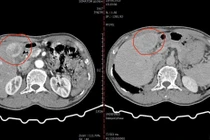

Một người đàn ông 66 tuổi mắc ung thư biểu mô tế bào gan (HCC) kèm nhiều bệnh nền nặng đã được Bệnh viện Đa khoa Trung ương Quảng Nam điều trị thành công bằng phương pháp can thiệp nút mạch hóa chất (TACE).

Hình ảnh khối u chụp cắt lớp vi tính trước can thiệp - Ảnh BVCC